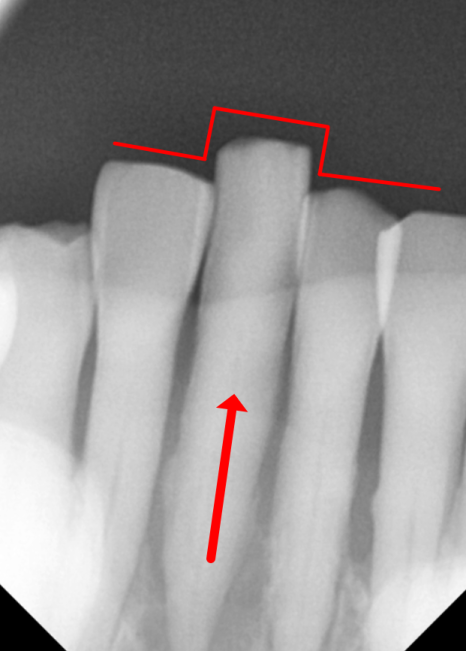

230609

그로부터 5개월 뒤,

임플란트와 뼈가 잘 붙었는지

수치로 확인하고 나서야

기분 좋게 본을 뜰 준비를 시작했습니다.

구강 스캐너 덕분에 본뜨기가

빠르고 정확합니다.

솟구치는 앞니, 흔들리는 치아가 보내는 '이 신호' 무시하면 안 되는 이유

"본뜨기"라고 하면,

이번 환자분도 구강 스캐너로 본을 떴는데,

정밀하게 스캔이 잘 돼서

보철이 당일에 바로 잘 맞았습니다.

230901

보통 임플란트 보철을 장착할 때는

높이, 맞물림, 간섭 등을 확인하면서

조금씩 조정하는 과정이 필요한데,

이번 케이스는 크게 조정할 게 거의 없었어요.

색상도 자연스럽고,

모양도 만족스러운 결과가 나왔습니다.^^